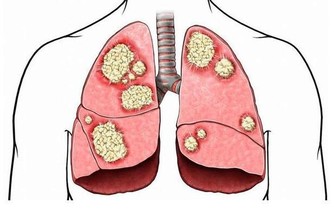

堅持讓他做個肺部CT,沒想到有肺部結節,進一步檢查確診原來是肺癌早期,

但是事實已經碰到好幾個病人檢查結果卻是肺內小結節,再進一步檢查原來是肺癌,

在過去的30年,我國肺癌死亡率上升了465%,

肺癌已經成為我國惡性腫瘤的第一位死亡原因,嚴重威脅大眾健康。

據統計,近50多年來,世界各國特別是工業發達國家,肺癌的發病率和病死率均迅速上升,

目前是全世界癌症死因的第一名,成為名副其實的“頭號殺手”。

肺癌的典型症狀是咳嗽、痰中帶血、胸痛等肺部表現,但是,約有半數肺癌患者一開始表現出在肺外的症狀。